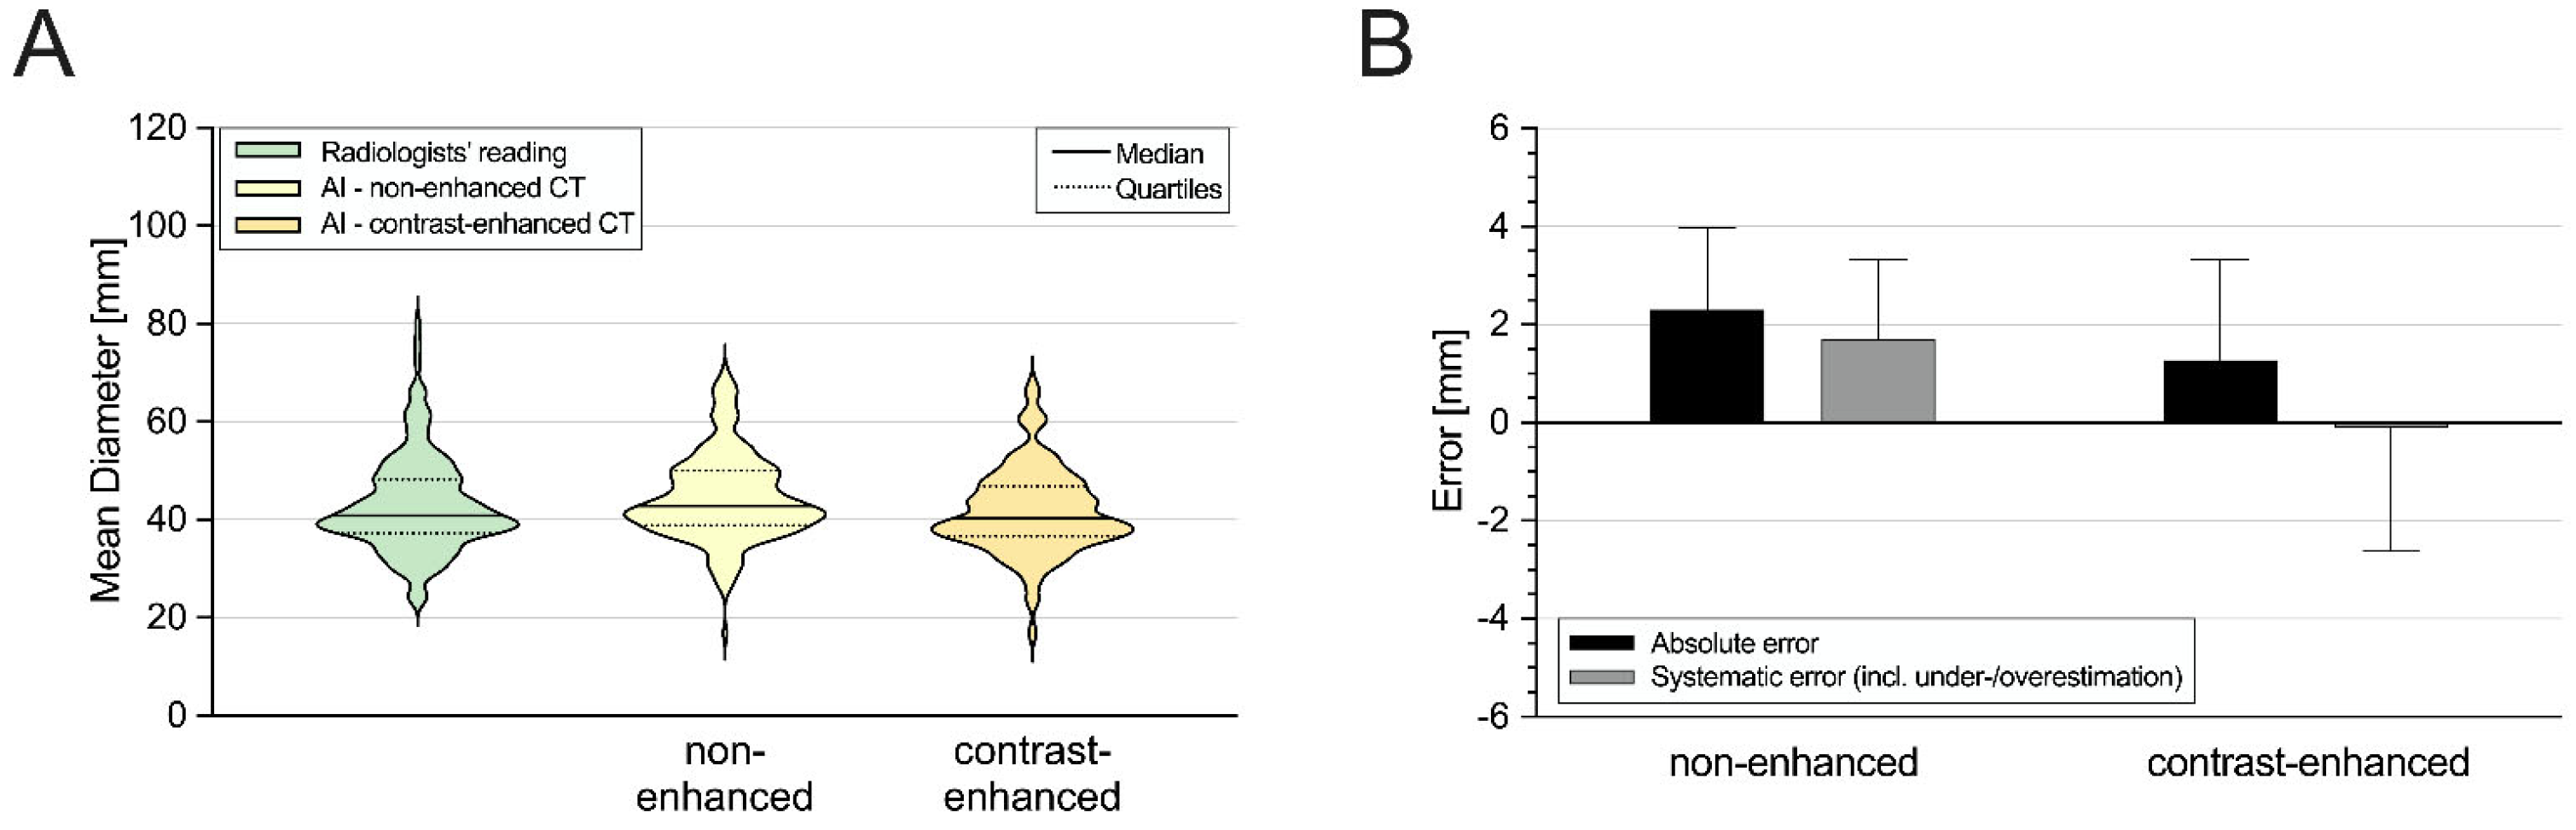

3.2. Aortic Diameter Quantification in the Entire Cohort